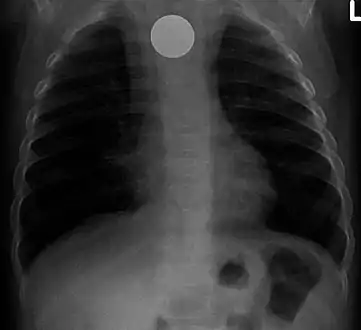

A coin seen on lateral CXR in the esophagus